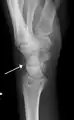

Triquetral fractures can occur due to forceful flexion of the wrist, causing an avulsion of the dorsal aspect of the bone that is often hidden on anterior radiographs, but can be seen as a tiny bone fragment on lateral views.

Triquetral fracture indicated by the white arrow.

Triquetral fracture as seen on lateral view of a radiograph.